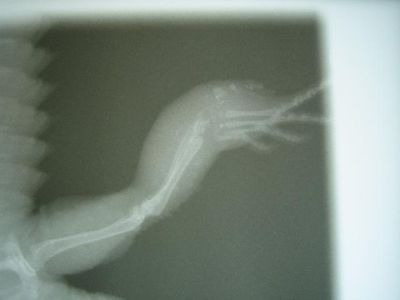

- Röntgenbild: Dornschwanzagame mit Abszeß im Mittelfußbereich und Osteolyse